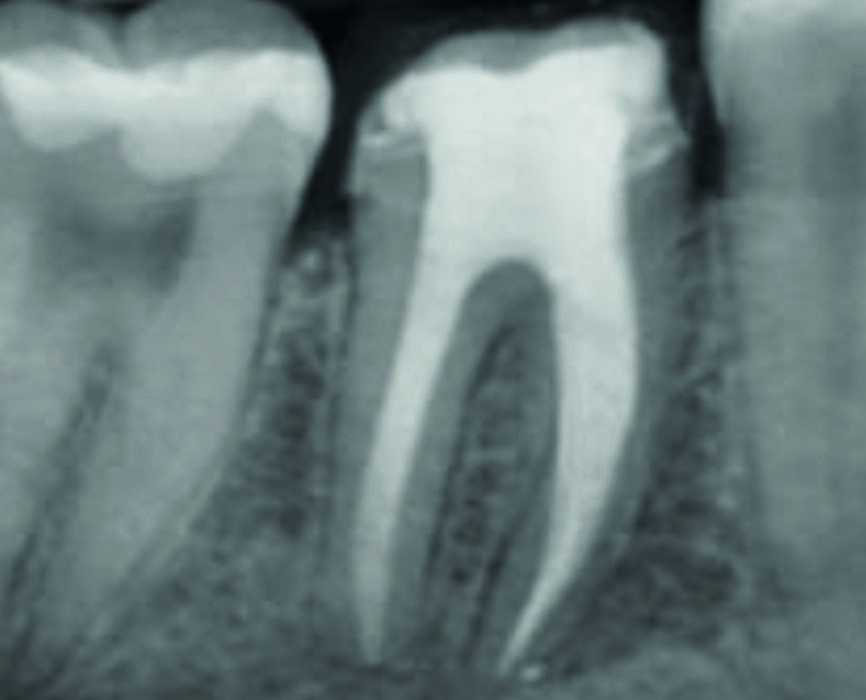

The calcium hydroxide paste was removed ten days later. The complete removal of paste from the root canal walls was accomplished by passive ultrasonic irrigation and 10% citric acid, using an endodontic tip (ESI, EMS) for more precise cleaning. Taking into consideration the extent of the apical root resorption, it was decided to perform orthograde MTA obturation of the distal canal space to arrest the resorption. The material was placed into the canals with the MAP System carrier (Produits Dentaires; Fig. 3) by the means of a 5 mm apical plug and was condensed vertically with a hand plugger. After radiographic examination of the accuracy of the apical plug (Fig. 4) and a setting period, the entire canal and the mesial canals were obturated with TotalFill BC (FKG Dentaire; Fig. 5). The orifices were adhesively sealed and the tooth was definitively restored with light-curing composite and prepared for a crown.

Fig. 4: Obturation of mesial canals and a 5 mm apical plug of MTA distally

Fig. 5: Control radiograph after final obturation